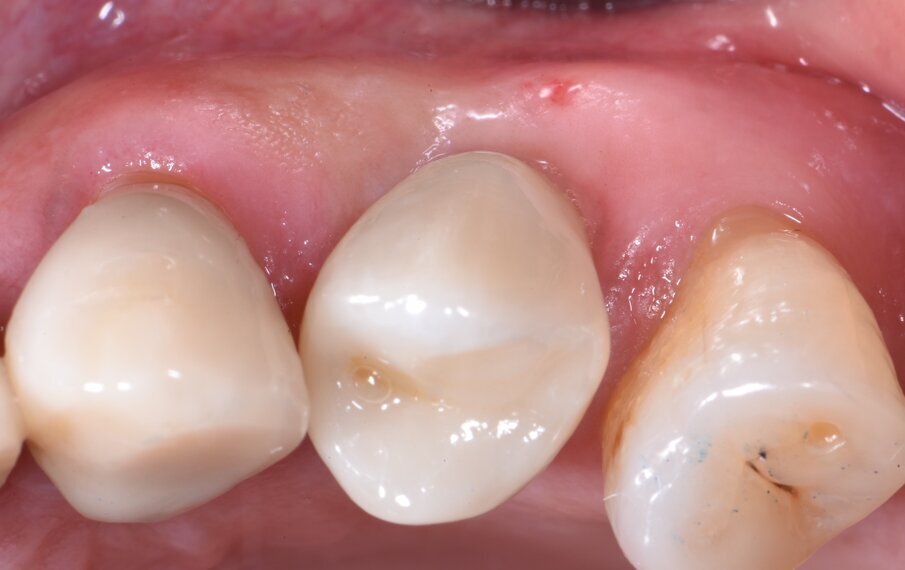

Fig. 3 - Si può notare il trofismo e il volume dei tessuti periimplantari 3 mesi dopo l’inserimento dell’impianto.

Fig. 2 - Coppetta di guarigione castomizzata avvitata sull’impianto appena inserito nell’alveolo post-estrattivo.